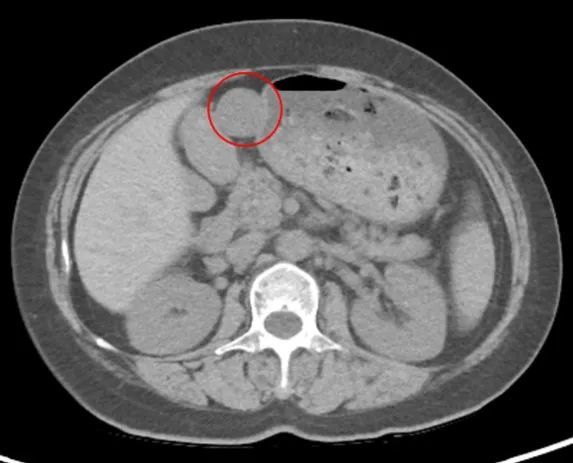

最近,冯阿姨总感觉胃不舒服,于是,在医生的建议下做了一个胃镜,突然发现胃里长了个小东西(如下图),随后,在熟人的介绍下,冯阿姨在家人的陪同下来河南省肿瘤医院普外科就诊,顺利完成手术,术后病理证实为胃肠间质瘤。

(右)CT显示胃壁长出来的圆形肿物